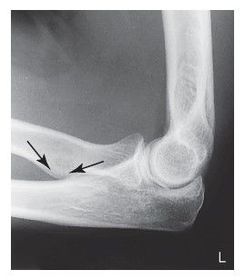

C. anterior fat pad D. posterior fat pad E. supinator fat stripe (not visible)

Which fat pad of the elbow will only appear on x-ray if there's a joint pathologic process? Posterior Fat Pad

Why does the elbow need to be in 90 degree flexion to determine whether the posterior fat pad is visible or not? When elbow is flexed more or less than 90 degrees it pushes the fat pad into different position, it can show up on x-ray then when there's no pathologic issue